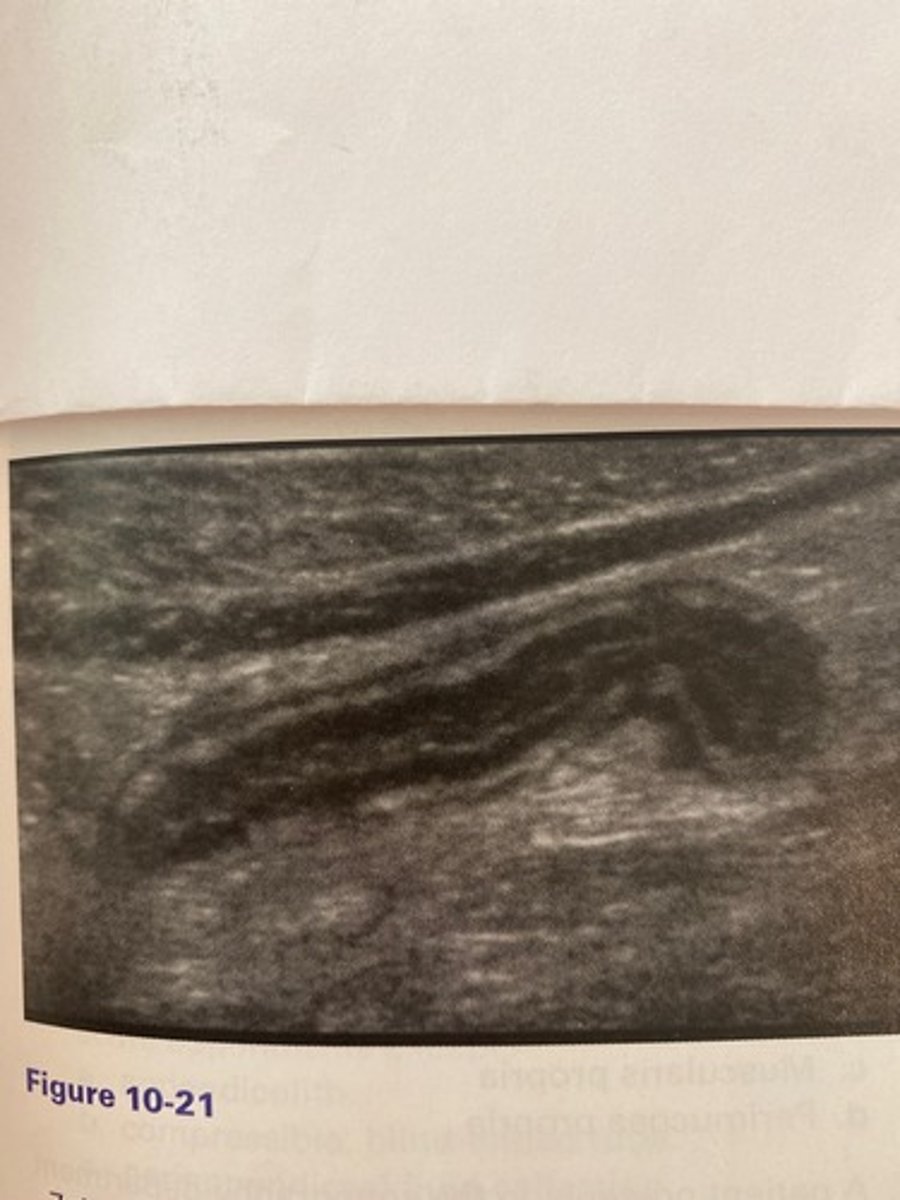

The patient in Figure 10-21 presented with right lower quadrant pain and nausea. The anteroposterior measurement of this structure in this image should not exceed:

a. 4 mm.

b. 3 mm.

c. 10 mm.

d. 6 mm.

b. Leukocytosis

Which of the following would be another common clinical finding for the patient in Figure 10-21?

a. Thyroid in the belly sign

c. Kernicterus

d. Hypernatremia

What is the thyroid in the belly sign?

a. Anechoic fluid surrounding an inflamed bowel segment

b. Hypochoic material adiacent to a distended pyloric stenosis

c. Enlargement of the distal colon in the presence of diverticulitis

d. Hyperechoic edematous connective tissue surrounding an inflamed appendix